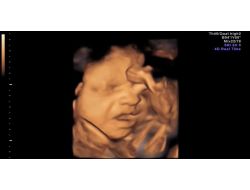

ANNE KARNINDAKİ BEBEĞİN ESNEMESİ GÖRÜNTÜLENDİ